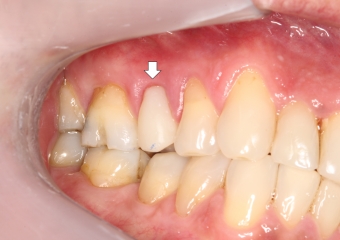

Foto extra oral frontal inicial

Provisório imediato